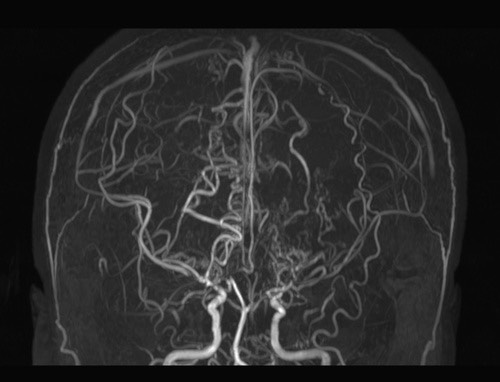

모야모야병은 뇌혈관, 특히 뇌로 혈액을 공급하는 내경동맥과 그 주변 주요 혈관이 점점 좁아지고 막히는 희귀 난치성 질환으로, 혈류가 줄어든 뇌는 부족한 혈액을 보충하기 위해 가느다란 미세측부혈관들을 새로 만들어냅니다. 이 작은 혈관들이 연기처럼 보인다고 하여 일본어로 ‘모야모야(안개·연기)’라는 이름이 붙었습니다. 소아부터 성인까지 폭넓게 나타나며, 특히 5~10세 어린이와 30대 전후의 여성에서 비교적 많이 발견되는 경향이 있습니다. 증상은 일시적 마비, 언어장애, 두통, 실신, 경련 등 매우 다양해 뇌졸중과 유사하거나 초기에는 가벼운 신경학적 증상으로만 나타나 진단이 늦어지기도 했습니다. 질환이 진행하면 허혈성 뇌졸중(뇌경색)이나 출혈성 뇌졸중 위험이 증가하여 반드시 전문적인 관리가 필요합니다. 아직 완전히 예방할 수 있는 방법은 없지만 조기 진단과 적절한 치료를 통해 뇌 기능을 보호하고 삶의 질을 유지할 수 있습니다.

모야모야병은 뇌기저부의 주요 혈관이 서서히 협착되고 막히면서 뇌혈류가 감소하는 만성 진행성 뇌혈관 질환입니다. 협착이 진행된 부위를 대신해 뇌는 생존을 위해 얇고 약한 혈관망을 만들어 혈류를 보충하려 하고, 이 새로운 혈관들이 촬영 영상에서 연기처럼 퍼져 보인다고 하여 ‘모야모야’라는 이름이 붙었습니다. 기전적으로는 내경동맥 말단부와 중대뇌동맥·전대뇌동맥의 기시부에 병변이 가장 잘 생기며, 시간이 지남에 따라 양쪽에 대칭적으로 나타나는 특징을 보였습니다. 이 질환은 단순한 혈관 협착이 아니라 진행성 변화이기 때문에 치료하지 않으면 혈류 부족이 심해지고 뇌 손상이 누적될 수 있습니다. 또한 뇌기능이 체력·호흡·체온 변화 등에 민감하게 반응하기 때문에 과호흡, 울음, 격렬한 운동, 감염 등으로 증상이 악화될 수 있습니다. 즉, 모야모야병은 시간이 지나면서 뇌혈류를 감소시키고 뇌졸중 위험을 높이는 질환이며, 평생 관리가 필요한 만성적 특성을 갖고 있습니다.